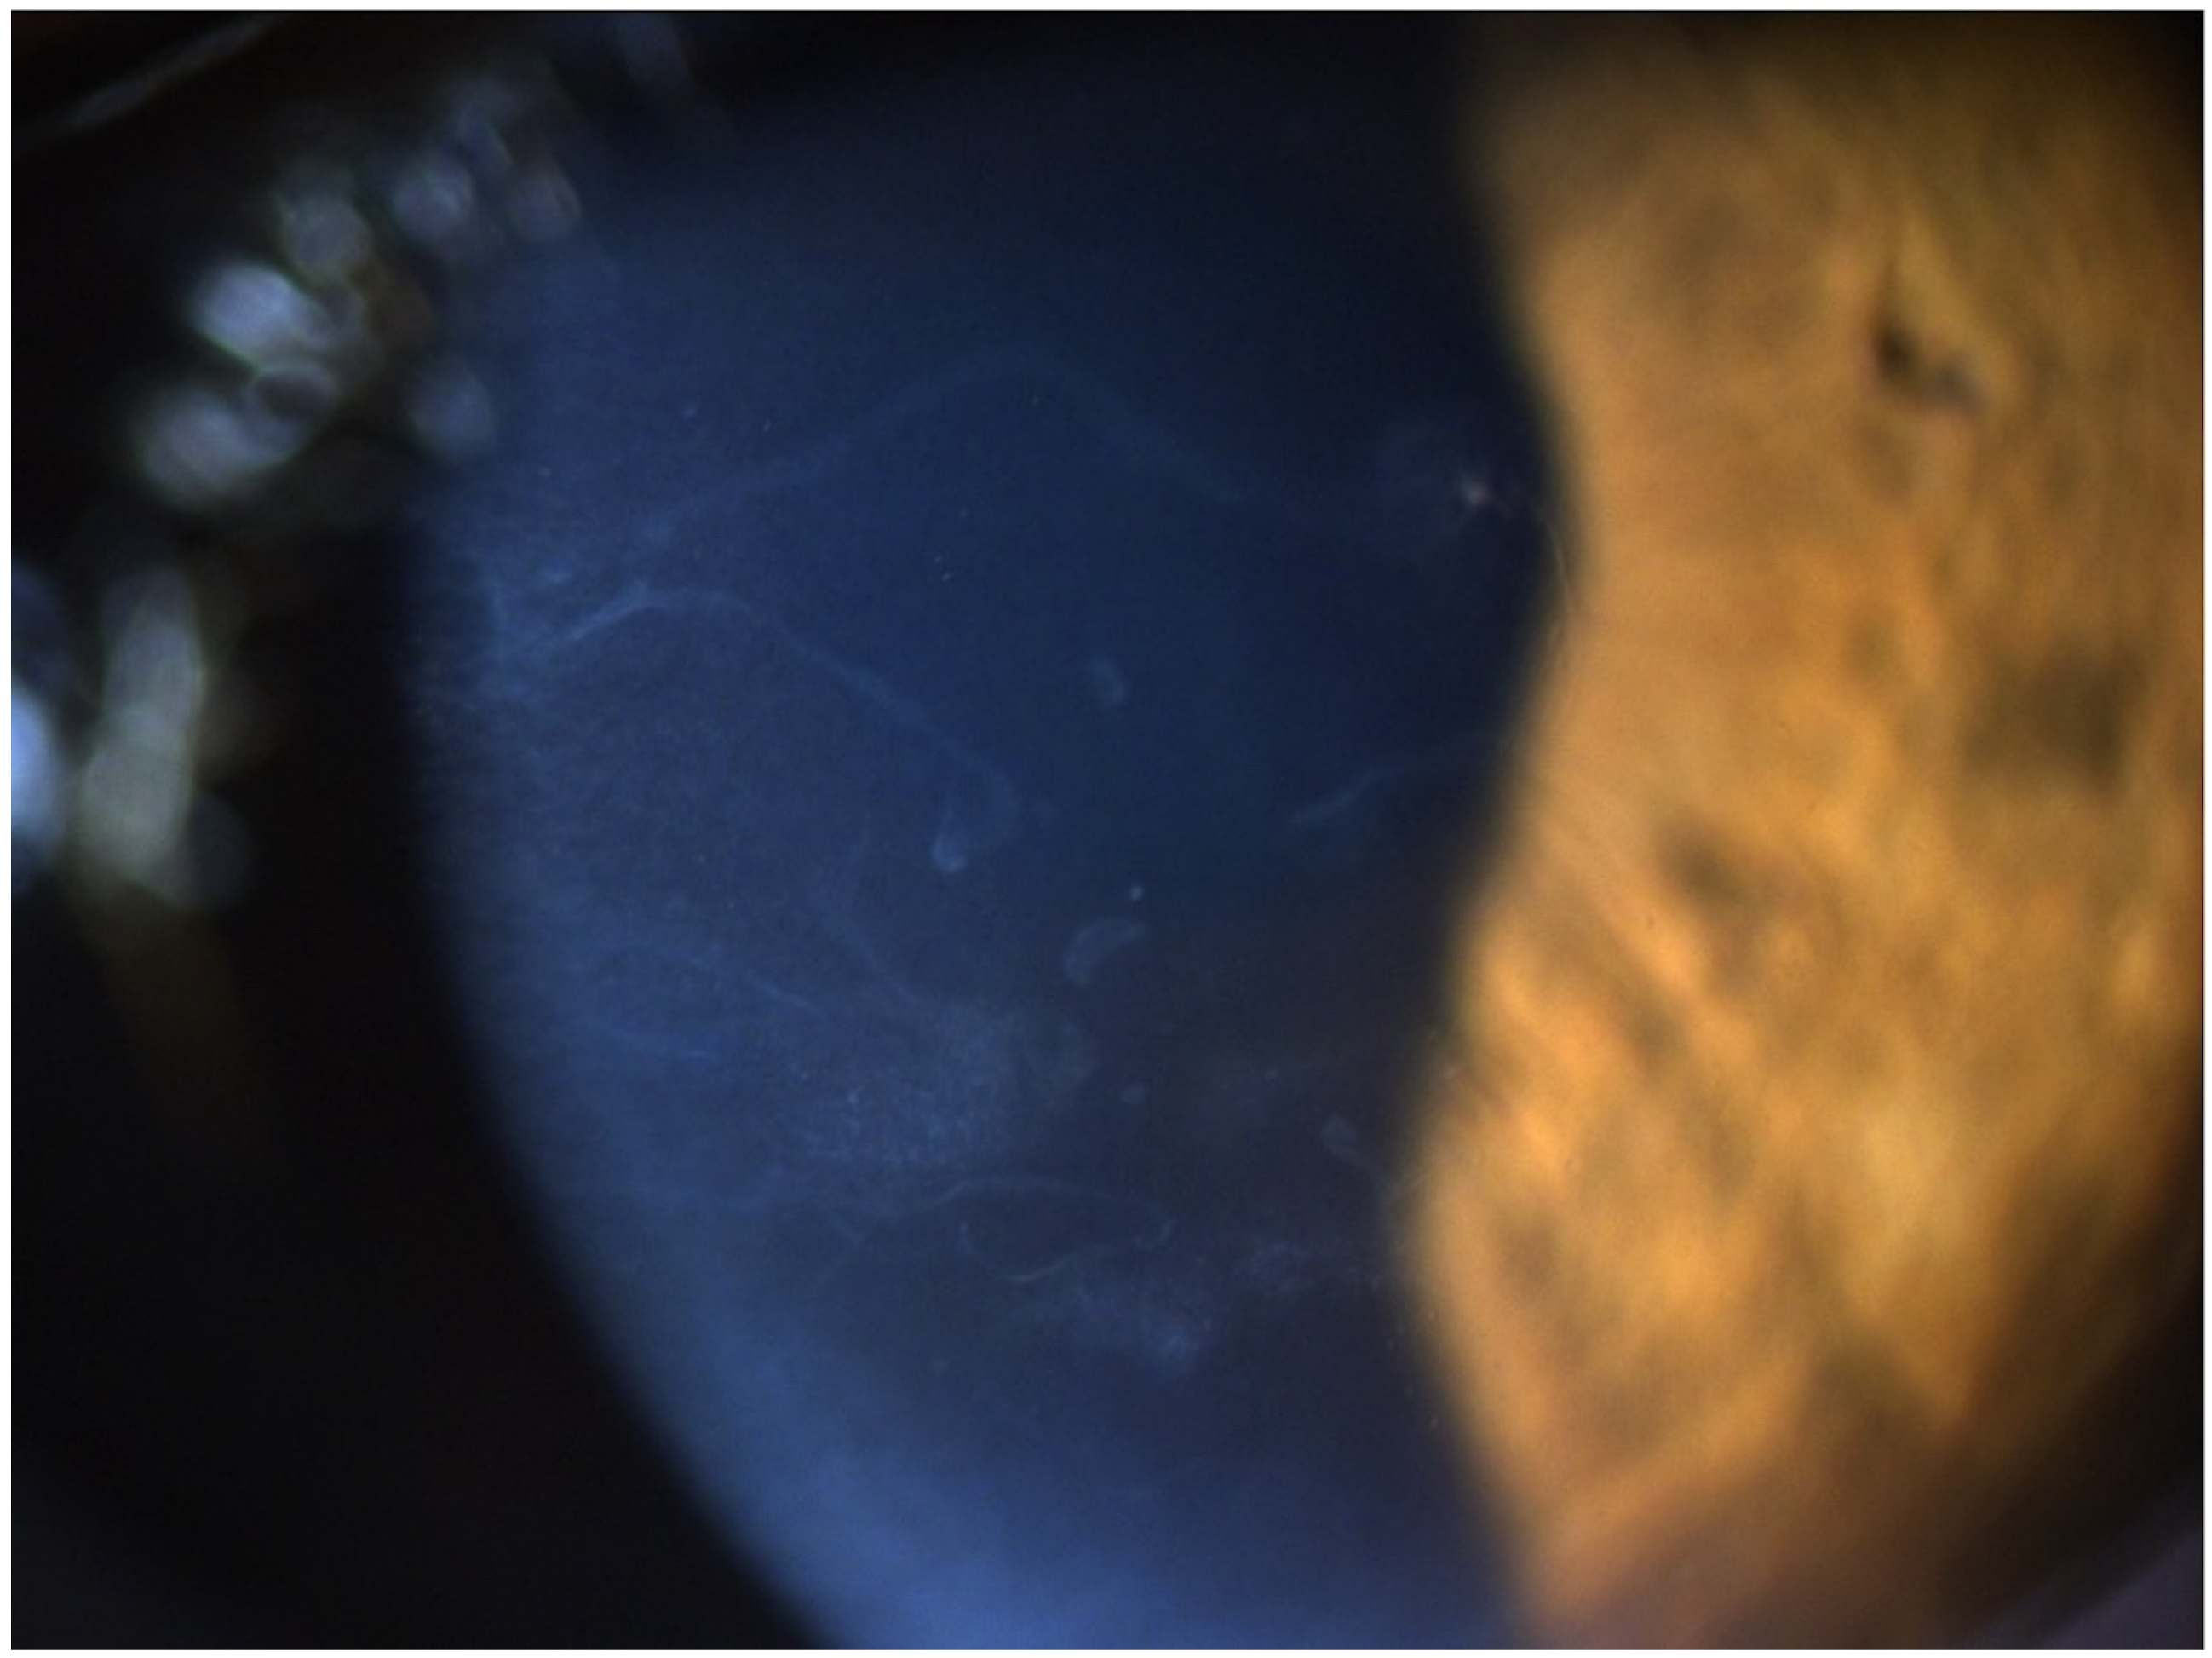

A 65-year-old female patient was diagnosed with Cogan dystrophy with uncorrected visual acuity (UCVA) of 20/30 in the right eye (OD) and 20/150 in the left eye (OS) and with distance-corrected visual acuity (DCVA) of 20/25 in the OD and 20/40 in the OS. Figure 3 shows the OS biomicroscopy with classical epithelium changes, and Figure 4 shows Pentacam OCT images (Scheimpflug, the actual shape of the cornea, and the cornea zoom, which corresponds to axial compaction) with abnormal epithelium layers.

Figure 3. Slit-lamp biomicroscopy of classical epithelium changes in the Cogan dystrophy.